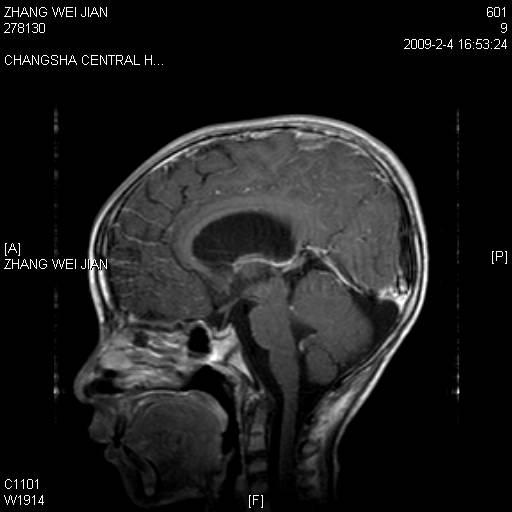

以下是引用随光逐影在2009-2-7 8:30:00的发言:[br]考虑双侧脑室脉络丛乳头状瘤并脑积水。

以下是引用同在2009-2-7 15:13:00的发言:[br]脉络丛乳头状瘤并脑积水。